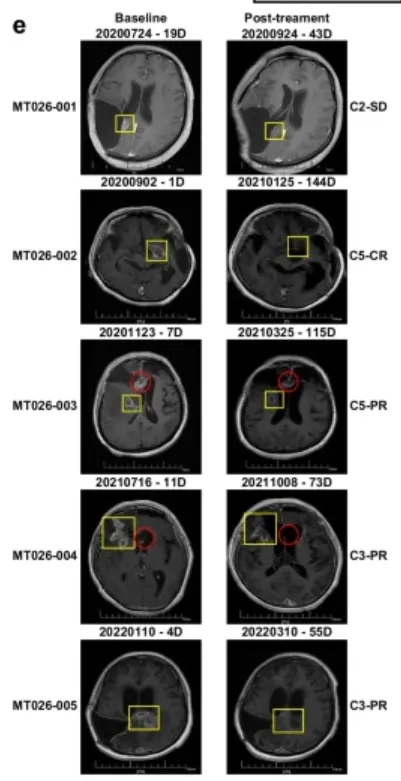

这项首次人体I期临床试验(试验编号:ChiCTR2000028801),共纳入5名复发高级别胶质瘤患者,这些患者均经过手术、放疗、替莫唑胺化疗等常规治疗失败,且病情危重,所有患者均为IDH野生型、MGMT启动子未甲基化(这两种都是预后极差的标志)。

客观缓解率80%:5名患者中,1名实现完全缓解(肿瘤完全消失),3名实现部分缓解(肿瘤明显缩小),1名病情稳定,没有1名患者出现病情进展,疾病控制率100%;

生存期大幅延长:从复发时间开始计算,患者的中位生存期达到13.1个月,12个月生存率80%,其中一名63岁的女性患者(MT026-002),复发后生存期更是达到了33.2个月,远超复发后6-8个月的中位生存期;